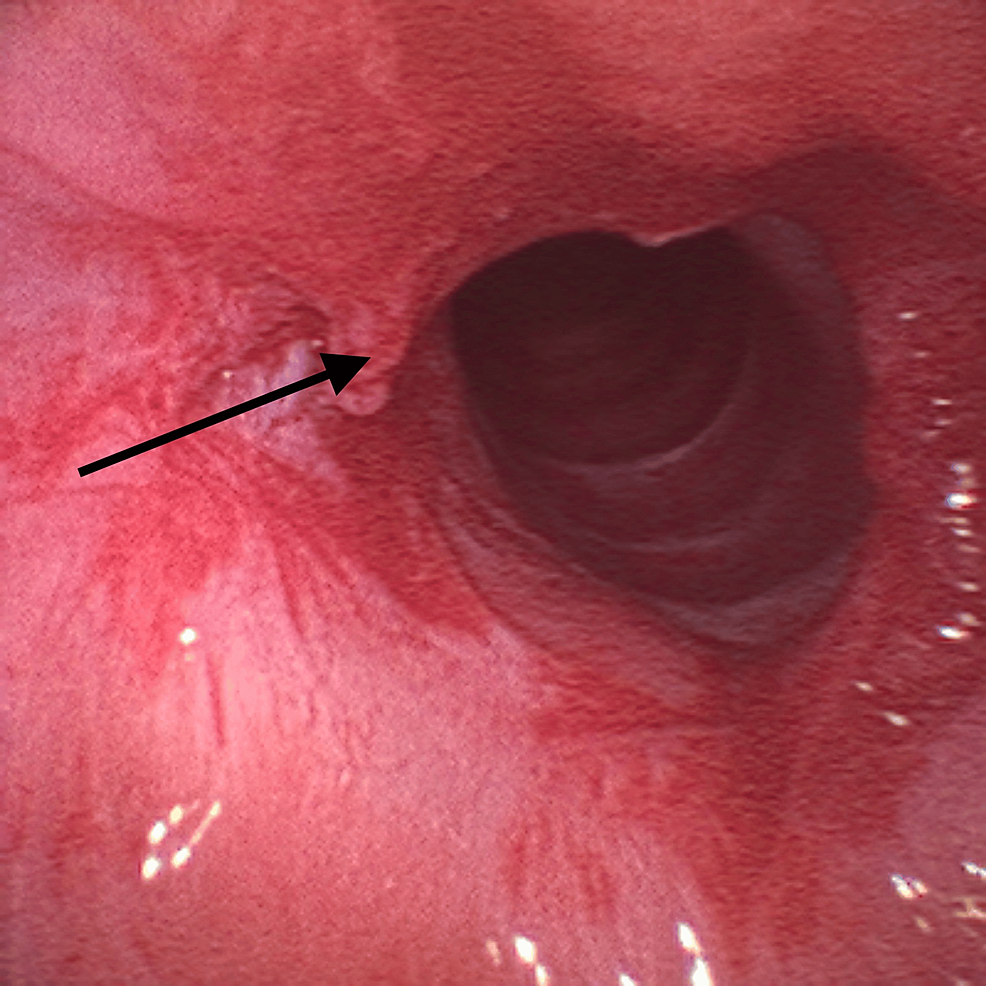

Given the findings, the supraglottic device was removed and the patient was placed in suspension laryngoscopy. Supraglottic manual jet ventilation was applied using a narrow-bore, noncompliant cannula attached to the rigid bronchoscope at one of the accessory ports on the head of the instrument. A maximum tracheal pressure of 35 cmH2O and a jet frequency of 10 per minute allowing adequate time for exhalation via passive recoil of the lung and chest wall preventing air trapping and barotrauma were applied. It was also performed with careful observation of the patient’s chest movements to ensure adequate tidal volumes without overdistension. Balloon dilatation with the application of mitomycin C was the elected otorhinolaryngologic technique (Figure 3) and at the end of the procedure, only a minimal portion of the membrane was noticed (Figure 4).